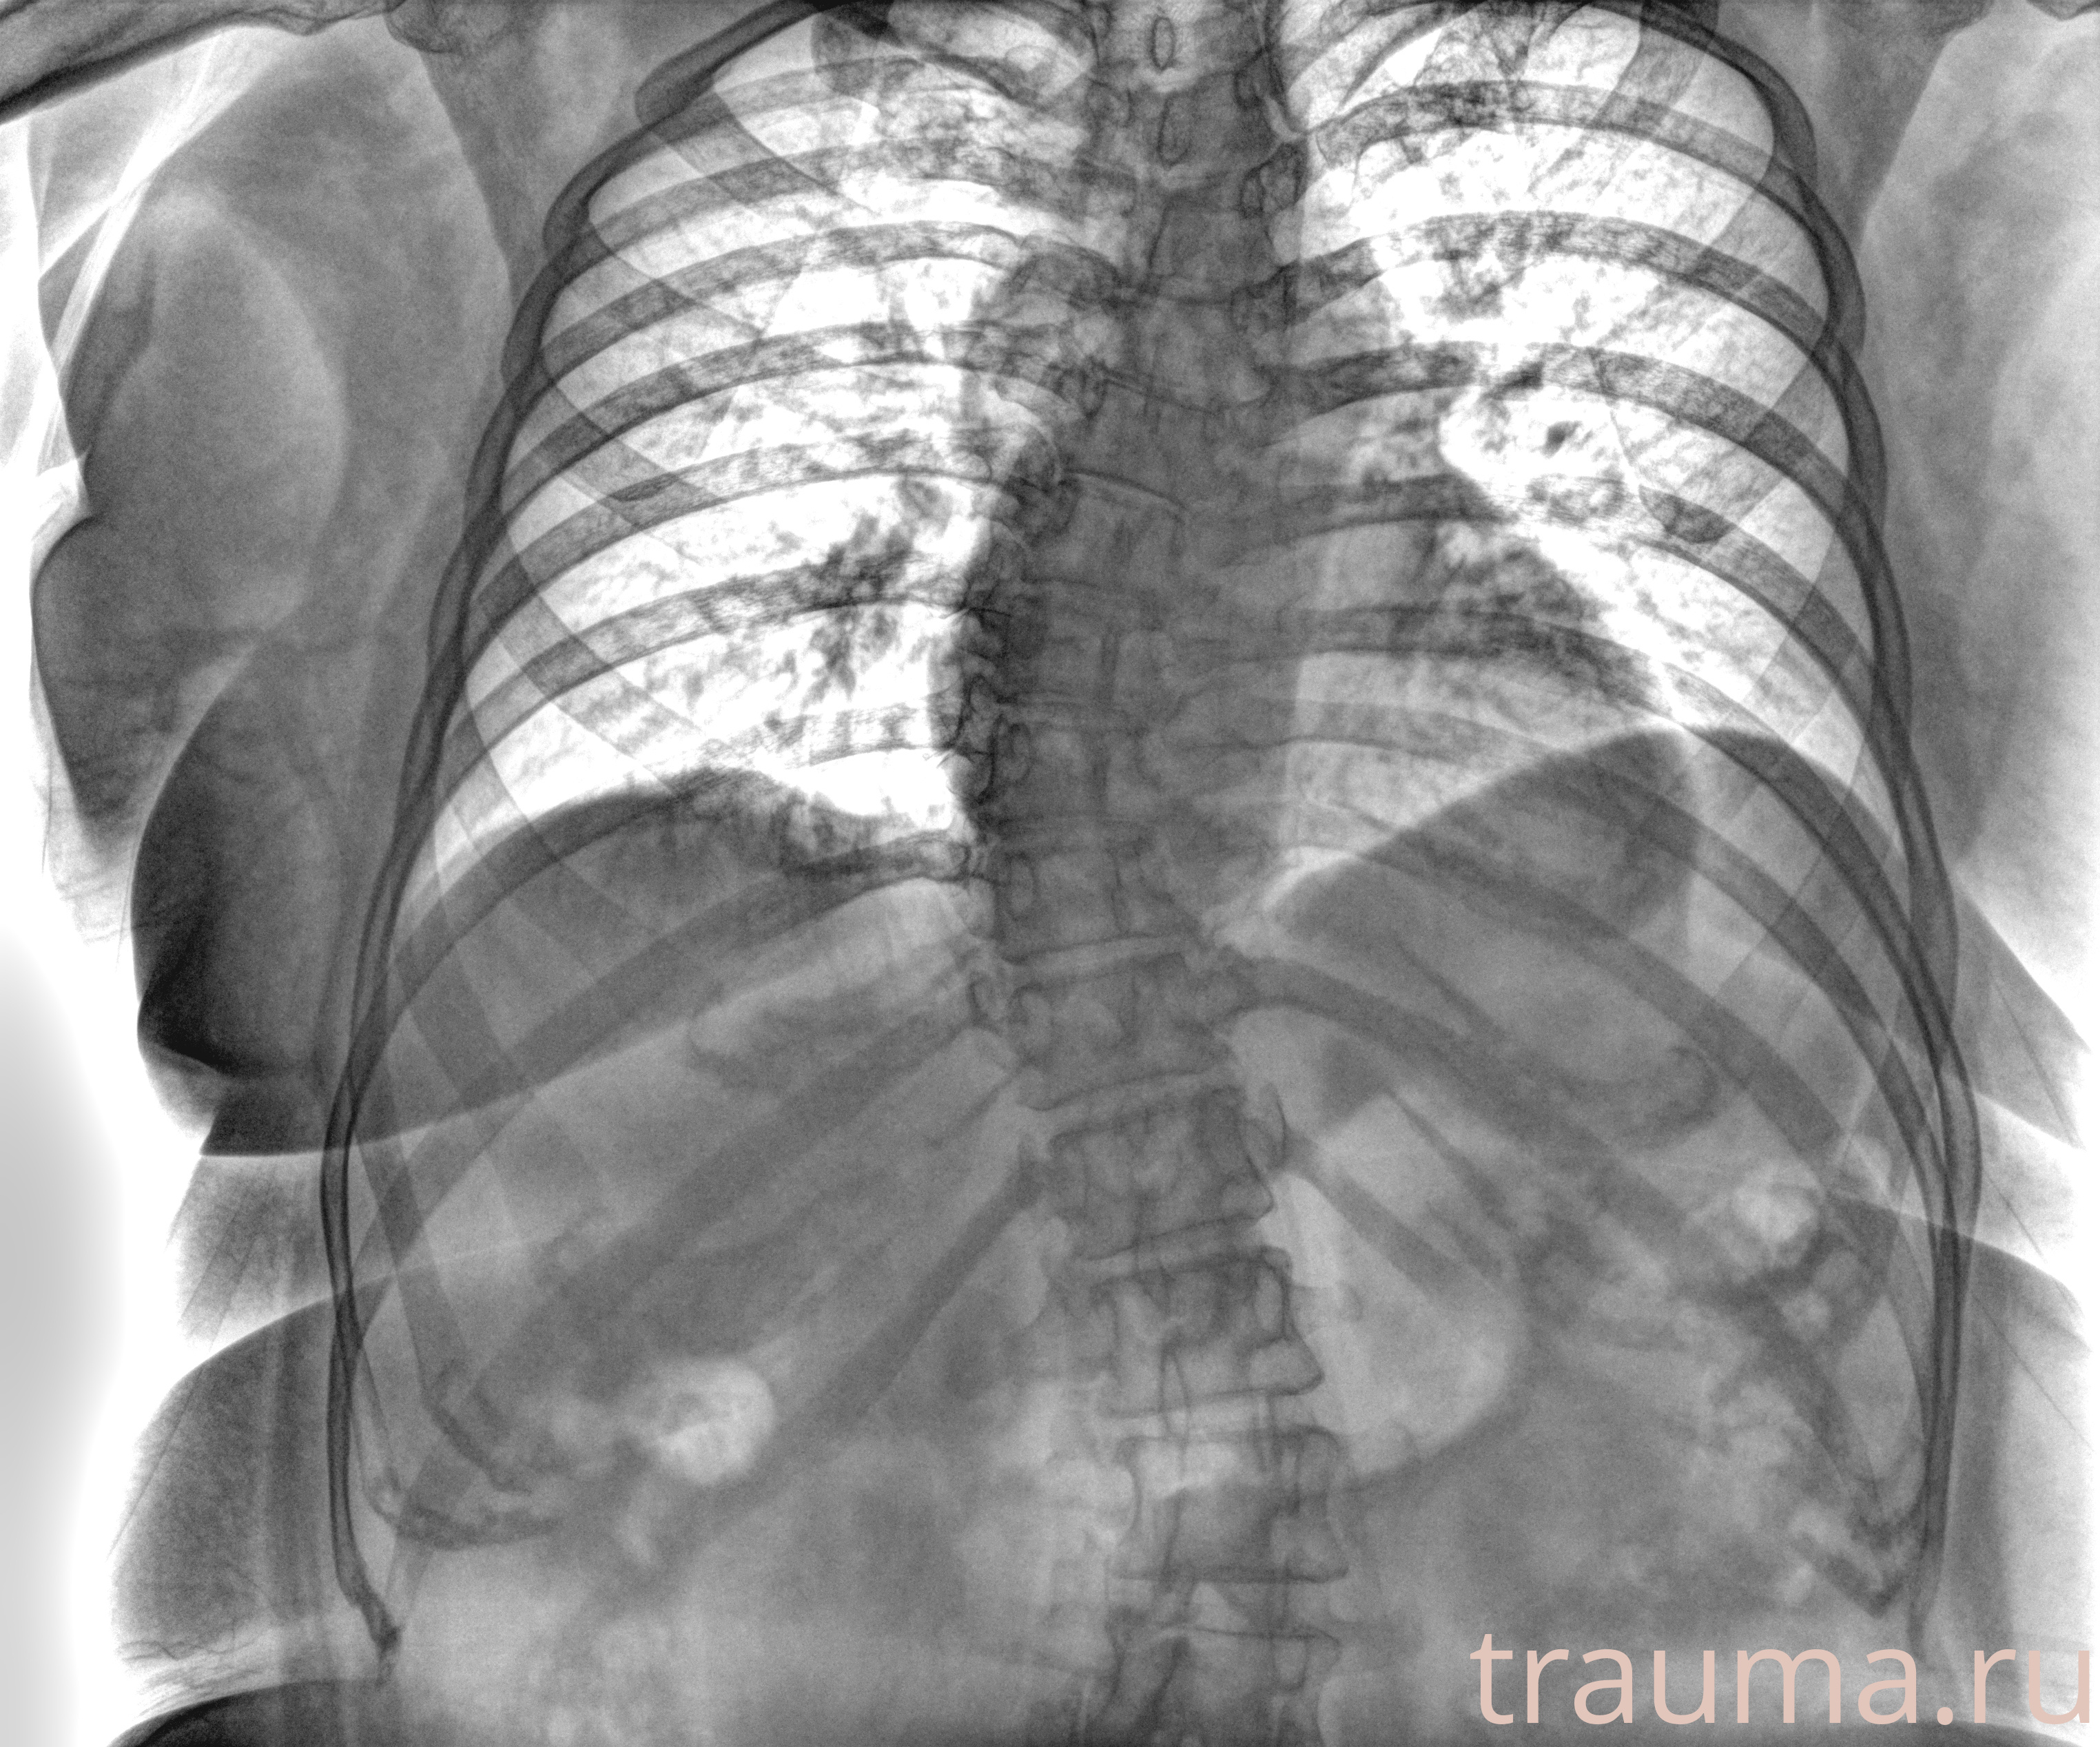

Рентген на дому: по вашему адресу приезжает врач-рентгенолог, травматолог-ортопед с мобильным рентгеновским аппаратом, проводит диагностику травмы или заболевания, делает необходимые рентгенограммы, дает рекомендации по дальнейшему лечению. Получить качественные снимки в домашних условиях возможно благодаря уникальной методике, разработанной МосРентген Центром для института  Склифосовского